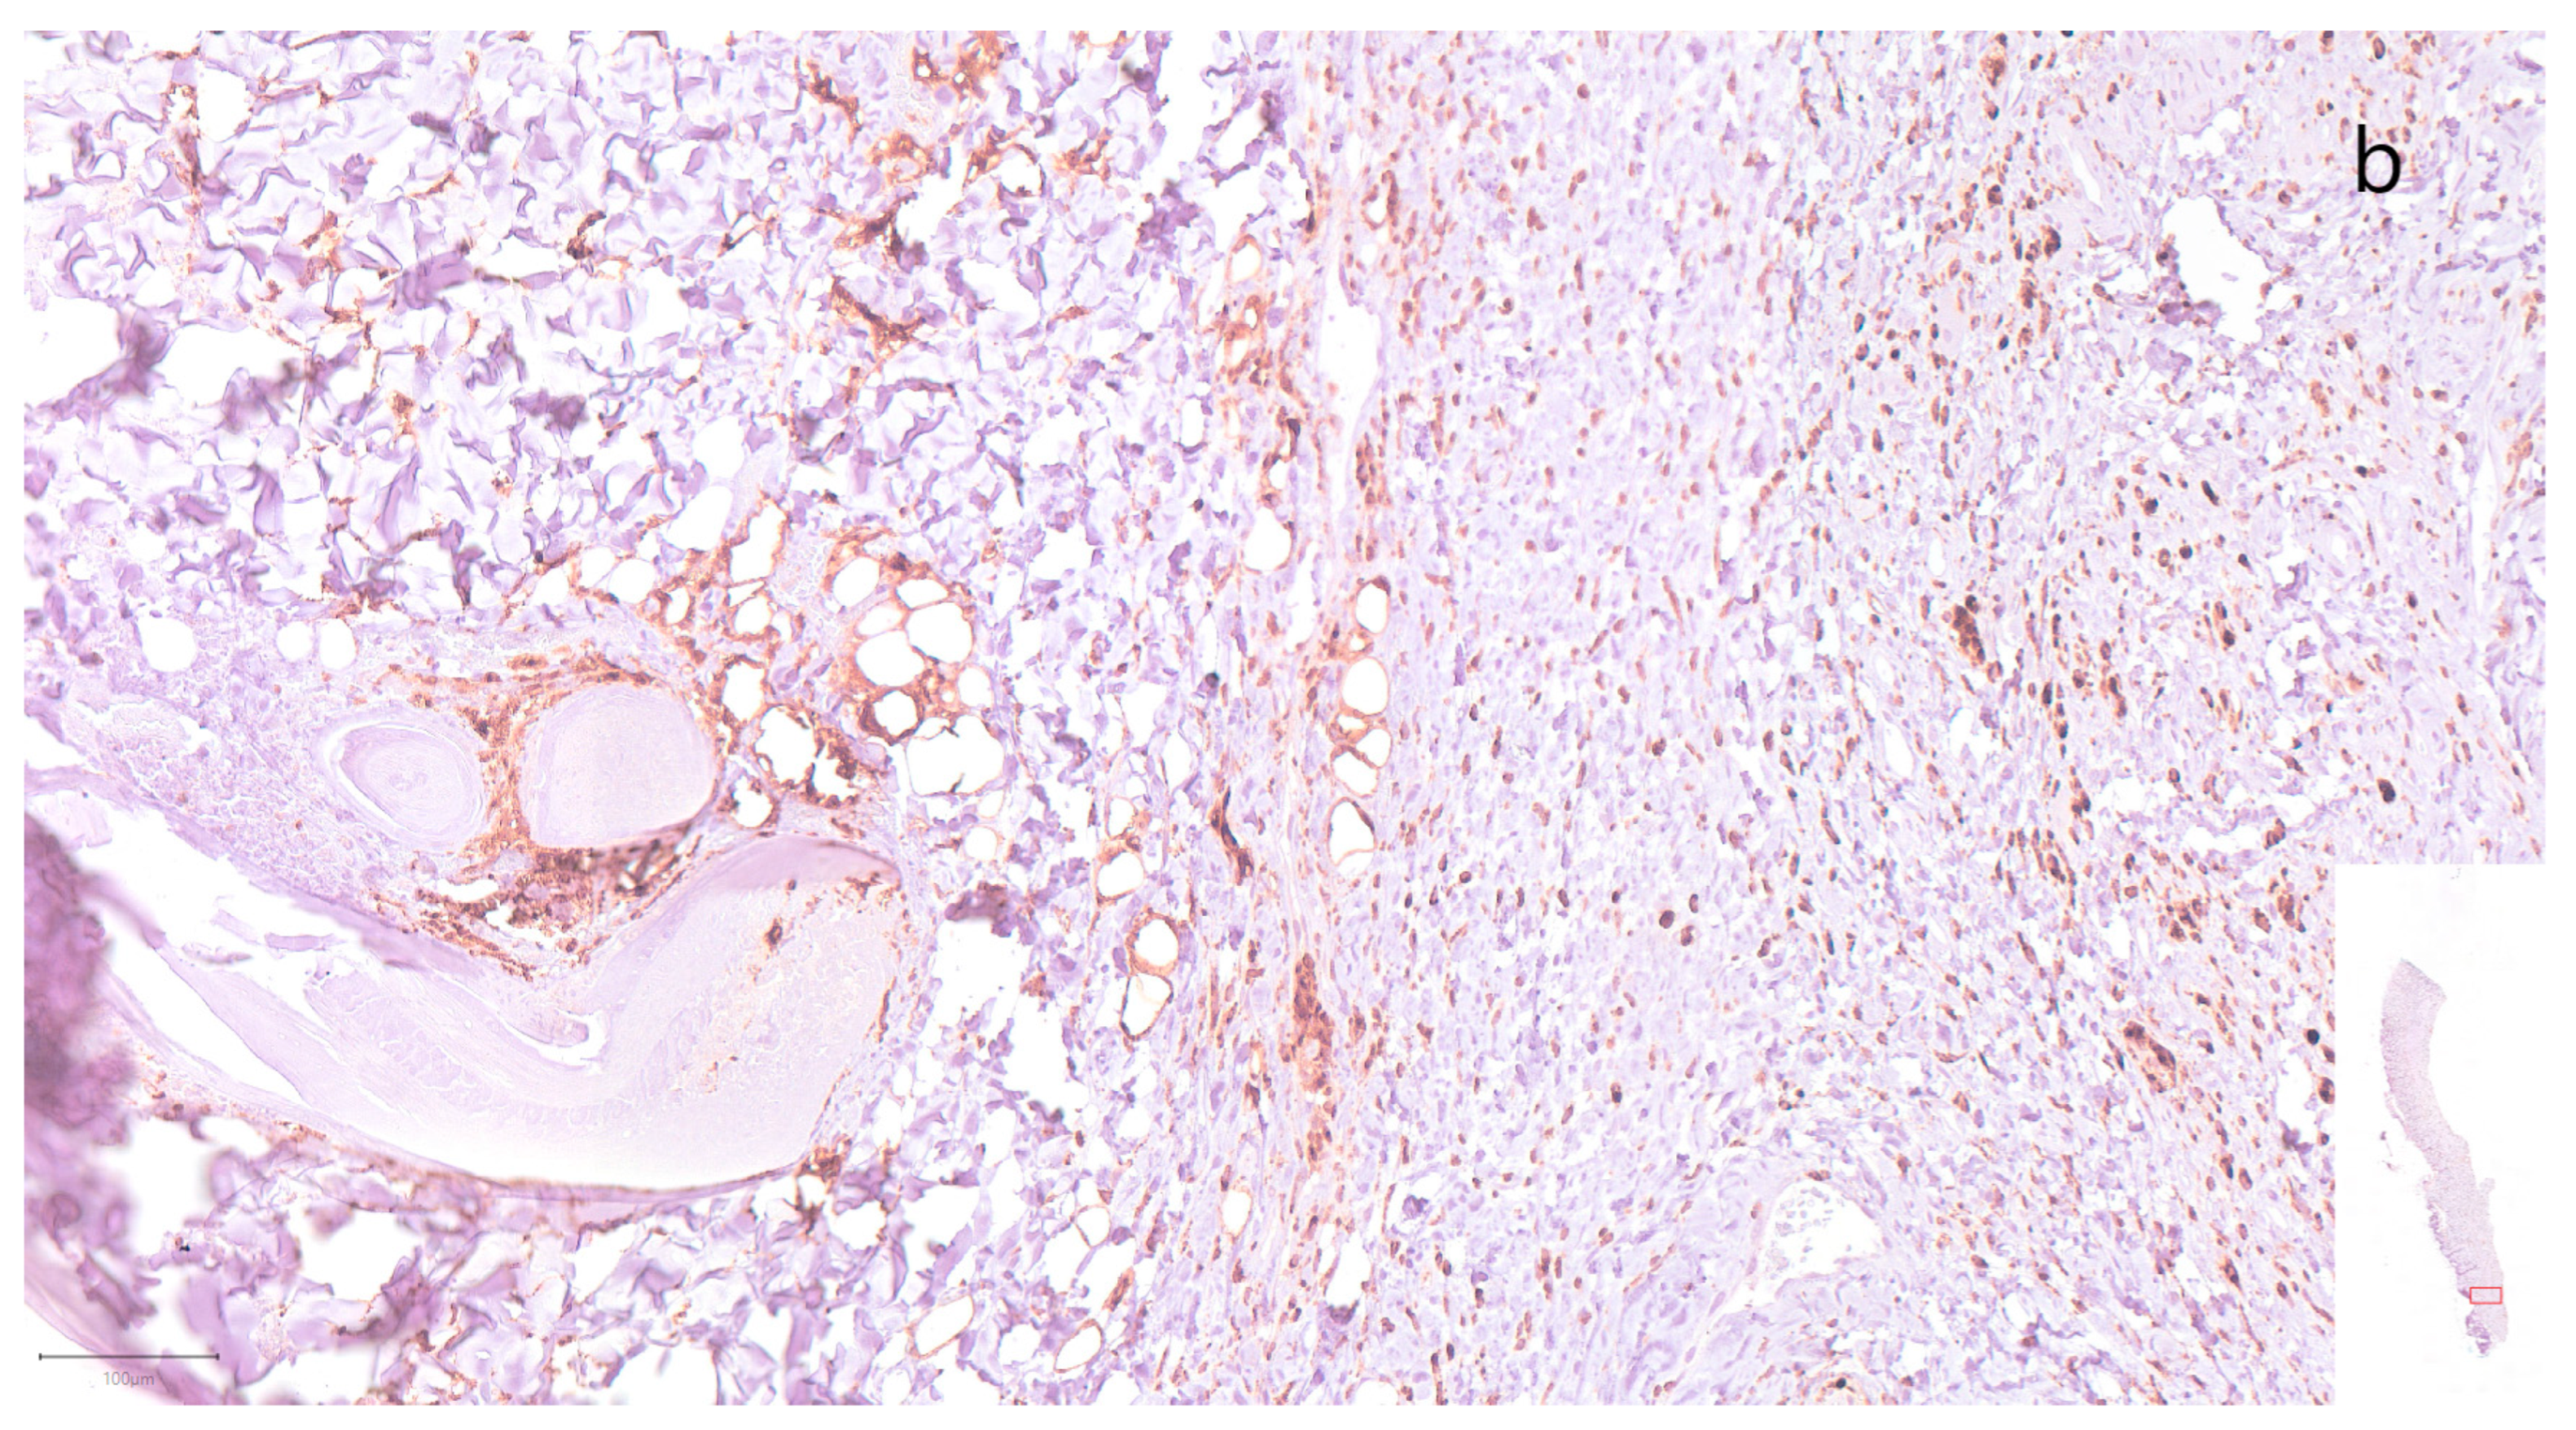

- Müller-Seubert, W.; Ostermaier, P.; Horch, R.E.; Distel, L.; Frey, B.; Cai, A.; Arkudas, A. Intra- and Early Postoperative Evaluation of Malperfused Areas in an Irradiated Random Pattern Skin Flap Model Using Indocyanine Green Angiography and Near-Infrared Reflectance-Based Imaging and Infrared Thermography. J. Pers. Med. 2022, 12, 237. [Google Scholar] [CrossRef] [PubMed]